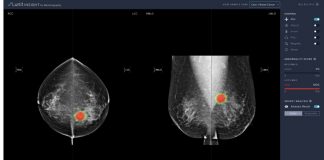

유방암 진단 AI 소프트웨어 ‘루닛 인사이트 MMG’ KFDA 허가

의료 인공지능(AI) 업체 루닛(대표이사 서범석)은 자체 개발한 유방암 진단 보조..